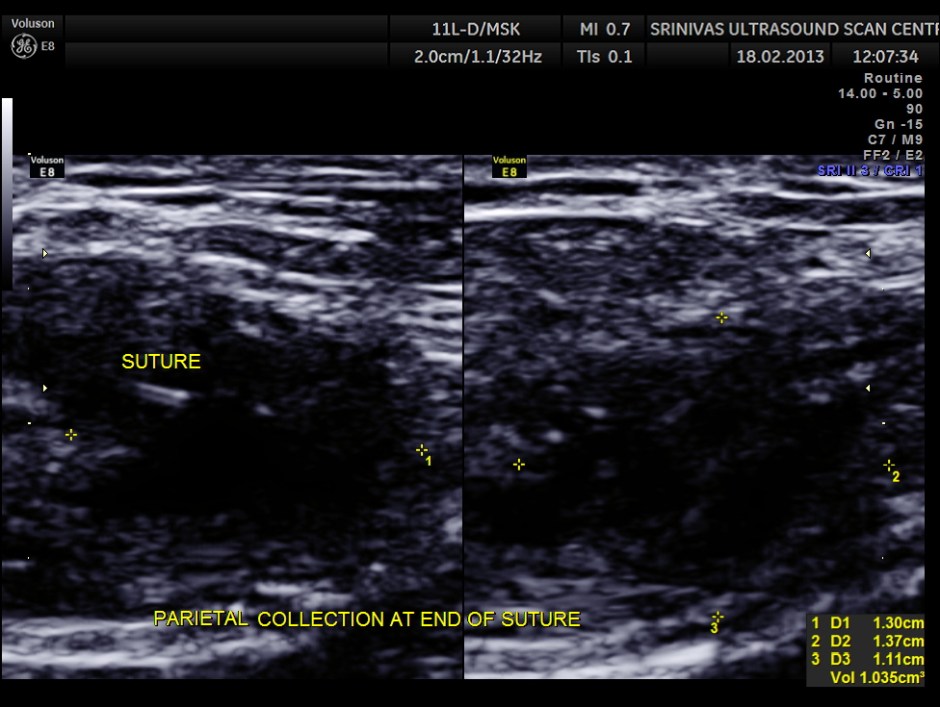

Her routine abdomino pelvic ultrasound scan was normal. The following pictures are acquired with a high resolution 11Mhz transducer.

This revealed unabsorbed suture and irregular collection